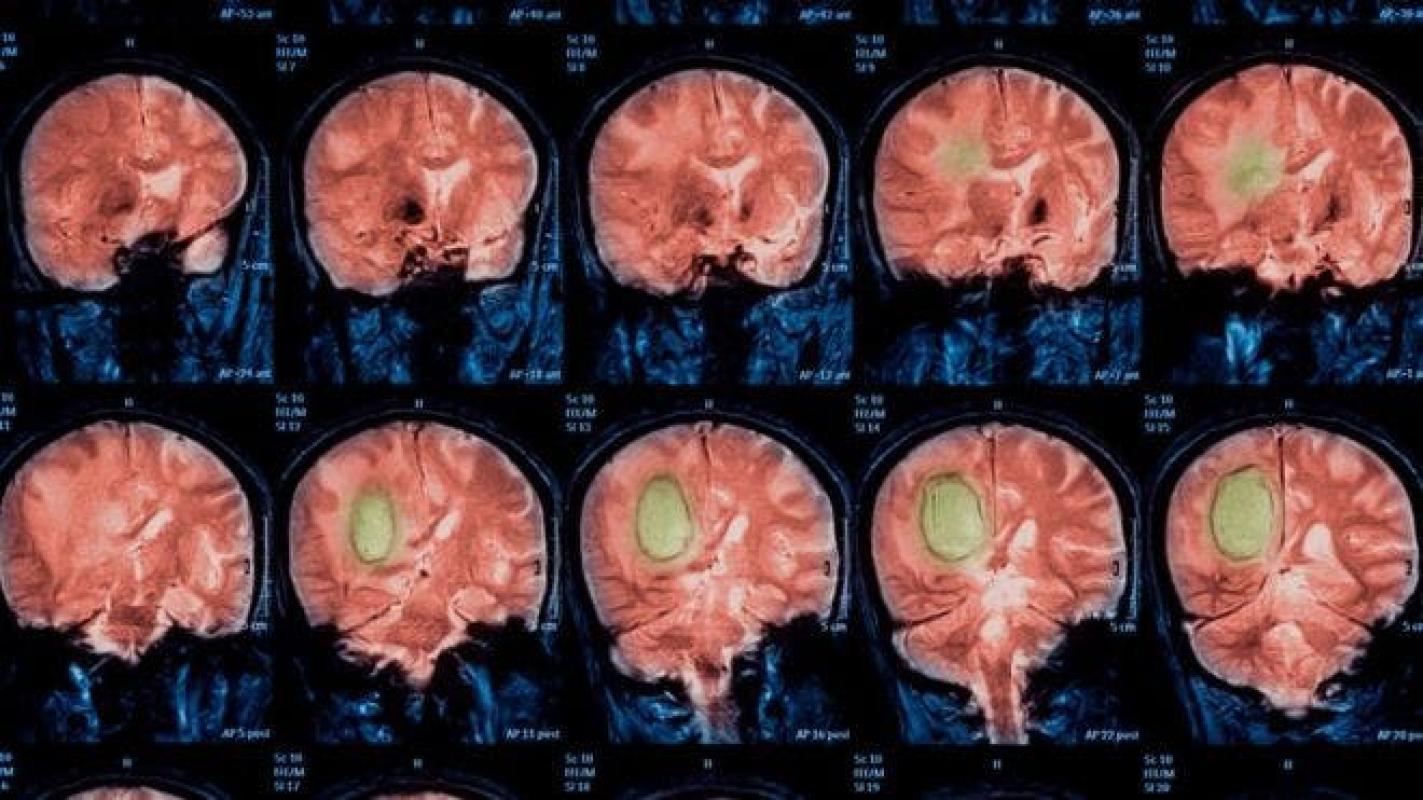

Desde que hace más de 20 años se empezaron a usar imágenes por resonancia magnética funcional (IRMf) para entender el comportamiento de nuestro cerebro, se han publicado unos 40.000 trabajos en el área de la neurociencia.

Hoy en día, muchos científicos utilizan IRMf para saber cómo reacciona nuestro cerebro a por ejemplo la música, videojuegos, violencia, amor, tristeza, etc.

Normalmente le piden a pacientes sanos que realicen una actividad y los expertos observan las áreas del cerebro que se iluminan.

Esos vóxel brillantes -el equivalente a los píxeles en imágenes 2D- aparecen gracias al programa informático que tiene la máquina. En realidad no están mirando el cerebro, sino una interpretación hecha por computadora.